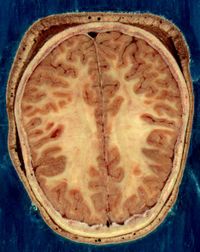

يتكون الجهاز العصبي المركزي من الدماغ والنخاع الشوكي ويقوم بتنظيم جميع أنشطة الجهاز العصبي والتحكم فيها. والدماغ عضو شديد التعقيد، يتكون من ثلاثة أجزاء أساسية هي: المخ والمخيخ وجذع الدماغ. وبهذه المقالة معلومات أساسية عن الدماغ. يعلو المخ كلاً من المخيخ وجذع الدماغ، ويلتف حولهما بدرجة ما، ويشكل نحو 85% من الدماغ، ويُعَدُّ الأكثر تعقيدًا. وللإنسان مخ متطور النمو، يقوم بتوجيه السمع والنظر واللمس والتفكير والإحساس والكلام والتعليم. يعلو المخيخ ـ والذي يقارب حجمه حجم البرتقالة ـ جذع الدماغ ويساعد الجسم في الاحتفاظ بتوازنه وينسق بين المعلومات الحسيّة وحركة العضلات. يشبه جذع الدماغ الساق، ويتصل بالنخاغ الشوكي في قاعدة الجمجمة. ويحتوي على العديد من العصبونات التي تتبادل المعلومات الواردة من الحواس. والكثير من العصبونات التي تنظم الوظائف التلقائية، مثل التنفس والنبض القلبي وتوازن الجسم وضغط الدم، توجد في جذع الدماغ. يتكون النخاع الشوكي من حبل من العصبونات التي تمتد من العنق وتتدلى حتى مايقرب من ثلثي العمود الفقاري، الذي يلتف حوله ويقوم بوقايته. ويحتوي النخاع الشوكي على السبل التي تنقل المعلومات الحسية للدماغ وتلك التي تتبادل أوامر الدماغ مع العصبونات الحركية.

ويسمى أيضًا الليف العصبي، ويشكل امتدادًا أنبوبيًا للجسم الخلوي للعصبون. وله العديد من التفرعات التي تمكنه من الاتصال بما يقرب من ألف عصبون آخر. وهو متخصص في نقل الرسائل. يبلغ طول المحوار داخل الجهاز العصبي المركزي أقل من مليمتر واحد، بـينما يزيد عن ذلك في الجهاز العصبي المحيطي، إذ يصل طول بعض المحاوير الممتدة من النُخاع الشوكي إلى عضلات القدمين إلى 75-100سم. أما الأعصاب فما هي إلا تجمعات لمحاوير عصبونات حركية أو حسية أو لكليهما معًا، التصقت مع بعضها مع بعض مكونة ذلك الشكل الحبلي. يغطي غمد مصنوع من مادة دهنية بيضاء تسمى الميلين بعض المحاوير، حيث تساعد على سرعة انتقال الدفعات العصبية عبرها، كما تساعد على التمييز بين المادة الرمادية والمادة البيضاء في الجهاز العصبي. وتتكون المادة الرمادية من محاوير غير مغطاة بالميلين وأجسام خلوية عصبونية، بينما تتكون المادة البيضاء من محاوير مغطاة بالميلين. وتصنع مادة الميلين في خلايا شفان في الجهاز العصبي المحيطي، بينما تقوم الخلايا الدبقية بتصنيعها في الجهاز العصبي المركزي.